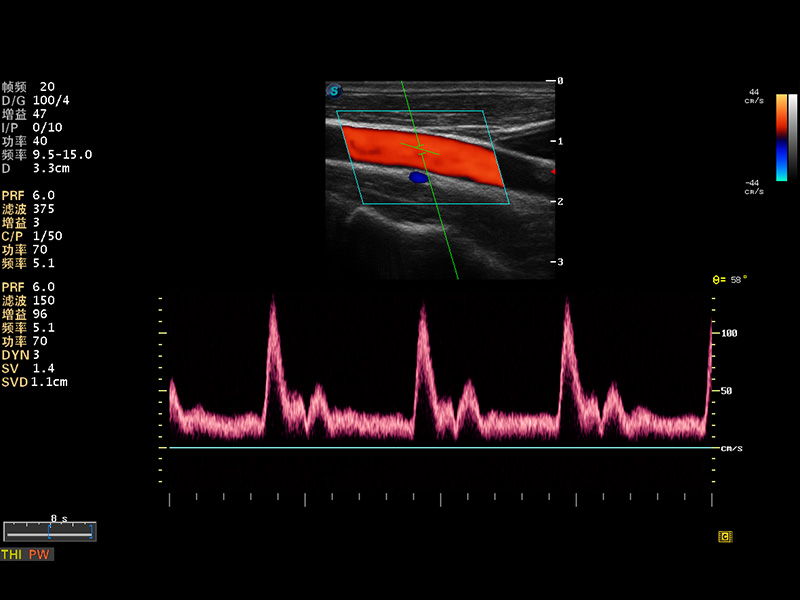

S8 EXP便攜式彩色多普勒超聲診斷儀是開立醫(yī)療研發(fā)的高端全身應(yīng)用型便攜彩超。高通道的VIS平臺融合可視化(Visual)、智能化(Intelligent)和人性化(Smart)的特點,配以開立醫(yī)療自主研發(fā)生產(chǎn)的探頭大家族,使您能夠快速、準確的獲得病人信息,提高工作效率的同時減輕疲勞。

成像技術(shù)

多波束形成器